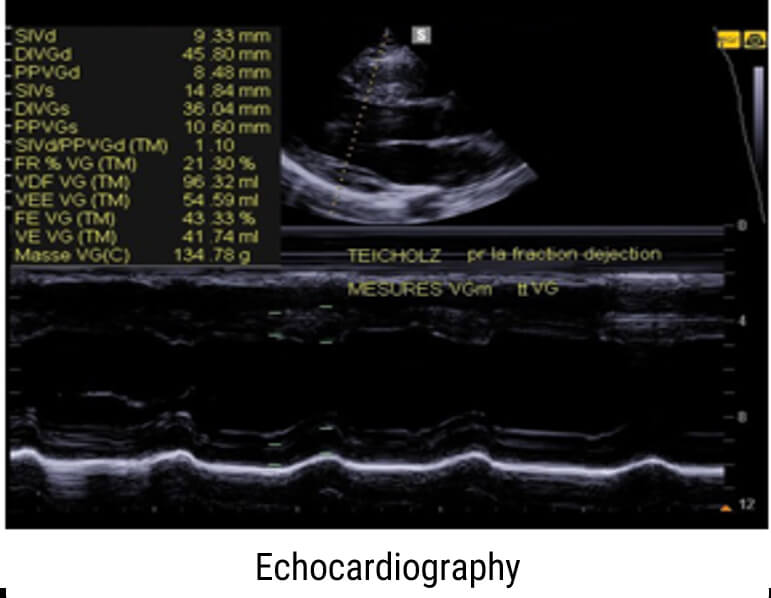

M-Mode

The M-Mode, or Motion Mode, is used to analyze moving body parts, and commonly used in cardiac and fetal cardiac imaging. It is based on the principle of recording the amplitude and rate of motion in real-time, by continually measuring the distance of the object from the single transducer at a given moment. The single sound beam is transmitted, and the reflected echoes are displayed as dots of varying intensities, thus creating lines across the screen.

The M-Mode (Motion Mode) is and commonly used in cardiography, where the direction of the beam is fixed and the returned echoes are recorded as a function of time.

Previously, we mentioned that the M-Mode is a unidirectional examination mode, that allows the analysis of tissue movement. This mode of representation is obtained by scrolling successive ultrasound signals corresponding to the same direction of the beam on a video monitor. The amplitude of the signal is coded in gray level, and useful in echocardiography for the analysis of heart valve movements.

Examples of Images

Here are some examples of M-Mode images, where the motion of the body part being scanned is displayed along the horizontal axis.